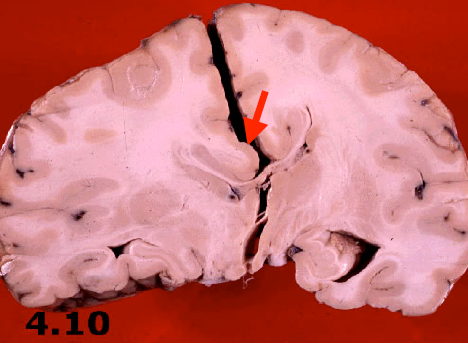

What is caused the area in the circle? What is the finding the arrow is pointing to?

Cystic cavity surrounded by gliotic tissue with glial strands (circle)

– There is compensatory (ex-vacuo) ventricular enlargement

What type of stroke caused this? What is the underlying vascular problem identified on pathology?

Lacunar infarction

• Infarctions ranging in size from 1 mm to 1.5 cm (arrow)

• Classically, the walls of small arteries become thickened from the formation of hyalinemembranes (lipohyalinosis) (circle)

– Caused by chronic hypertension